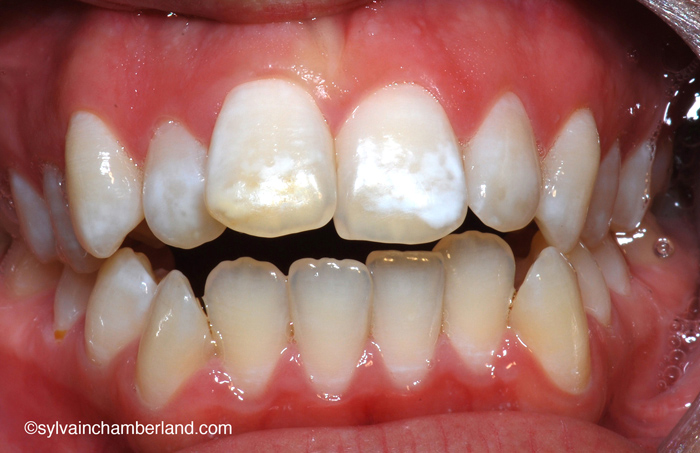

La photo à gauche représente une béance antérieure.

La radiographie à droite montre des condyles de formes normales.

Dans ce cas-ci la béance s’explique par un excès vertical du maxillaire. Observez, sur la radiographie céphalométrique de gauche, la grande distance entre les racines des dents postérieures supérieures et le palais. C’est l’indication d’un excès vertical. La longueur de la branche montante est normale et l’angle goniaque est à la hauteur de la 2e vertèbre cervicale.

Vous pouvez aussi comparé avec le tracé céphalométrique du cas précédent avec résorption des condyles. Il est facile de constater que l’angle goniaque est au niveau de C2 et que l’espace oropharyngé est plus large.

Ces deux cas illustrent une malocclusion avec béance antérieure, mais deux étiologies totalement différentes. Dans le 1er cas, la béance antérieure s’explique par la résorption condylienne. Dans le 2e cas, la béance s’explique par un excès vertical du maxillaire supérieur.

Le cas avec résorption a nécessité le remplacement des articulations par des prothèses totales customisées.

Le 2e cas a subi une chirurgie orthognathique bimaxillaire conventionnelle avec repositionnement supérieur du maxillaire, ostéotomie mandibulaire et génioplastie.